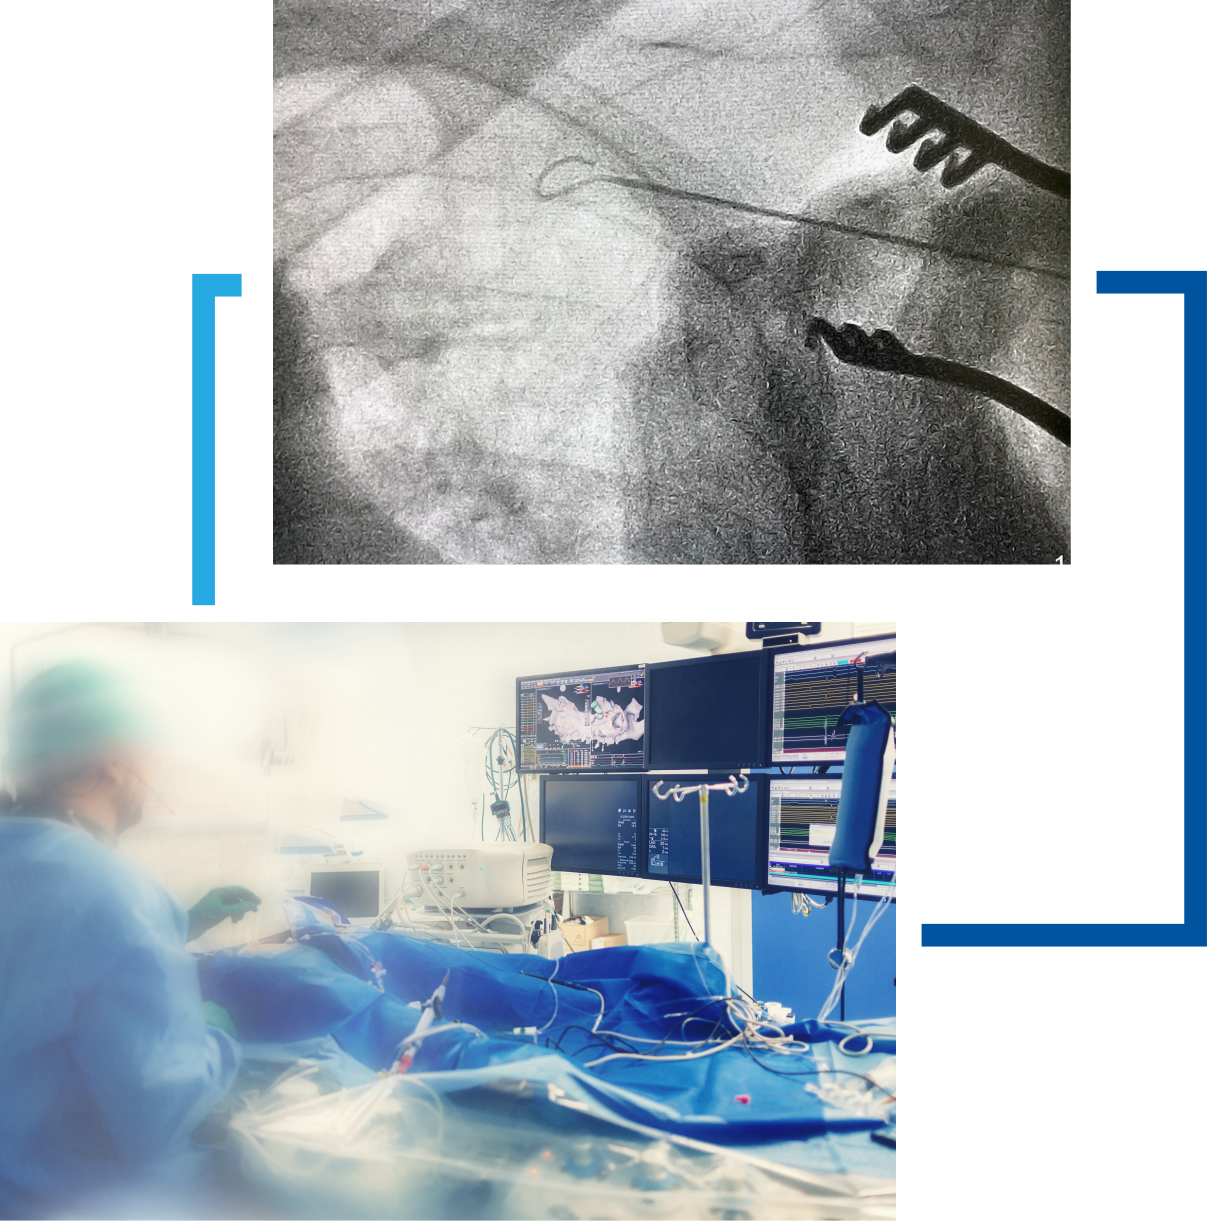

Electrofiziologia este o supraspecializare in cardiologie, fiind centrata pe studiul activitatii electrice a inimii - impulsurile electrice care controleaza activitatea muschiului cardiac si ajuta la pomparea si circulatia eficienta a sangelui.

Ablatia prin radiofrecventa

Ablatia prin radiofrecventa este o procedura minim invaziva utilizata pentru a trata aritmiile cardiace prin distrugerea tesutului cardiac anormal care genereaza ritmuri neregulate.